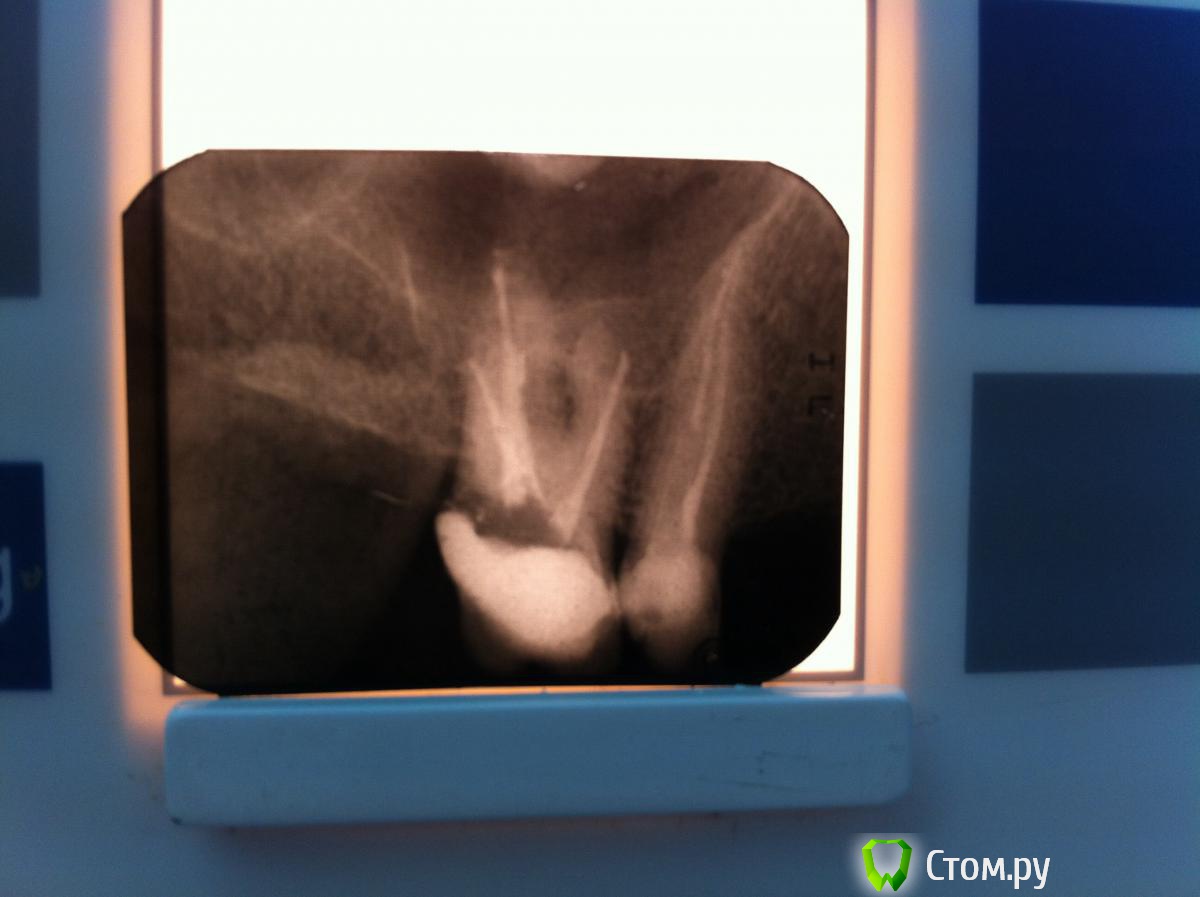

kukolenOk Опубликовано 12 ноября, 2013 Поделиться Опубликовано 12 ноября, 2013 Зуб 1.6, ранее лечен резорцин-формалиновым методом, в дальнейшем пойдет под коронку, что делать в таких случаях: не трогать каналы вообще, либо есть другие варианты? Ссылка на комментарий

ger_berra Опубликовано 12 ноября, 2013 Поделиться Опубликовано 12 ноября, 2013 (изменено) Множественные перфорации...К хирургу. Изменено 12 ноября, 2013 пользователем ger_berra 3 Ссылка на комментарий

Stom87 Опубликовано 12 ноября, 2013 Поделиться Опубликовано 12 ноября, 2013 Как можно было сделать столько перфораций? Захочешь - не получится Ссылка на комментарий